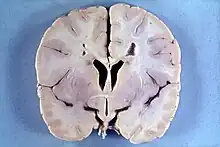

| An MRI of a patient with benign familial macrocephaly (male with head circumference > 60 cm) | |